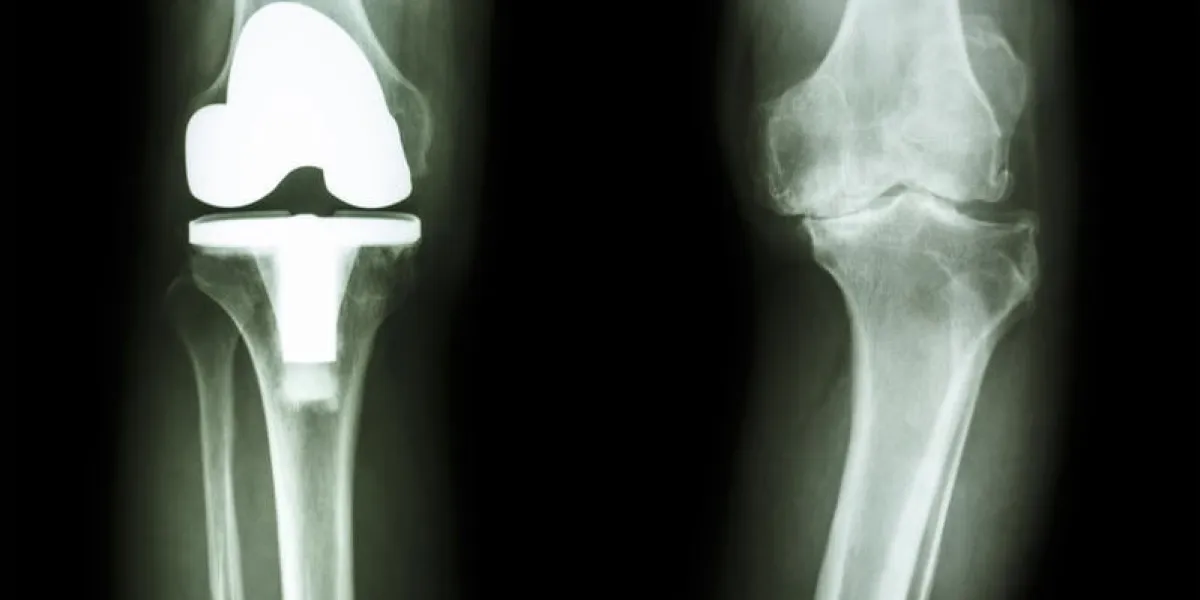

Bienvenue dans notre rubrique dédiée aux rhumatismes et aux problèmes articulaires. Cette section vise à fournir des informations complètes sur les affections rhumatismales, les douleurs articulaires, et les moyens de les prévenir et de les gérer. Explorez nos ressources pour comprendre les différents types de rhumatismes, les symptômes, les facteurs de risque, et les options de traitement disponibles. Nous sommes là pour vous accompagner dans la compréhension de ces conditions, pour vous donner des conseils pour soulager la douleur, et pour promouvoir une meilleure santé articulaire.